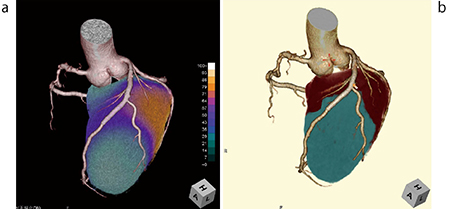

CT/SPECT心臓フュージョンでは冠動脈解析でのWKSを使用し、stress rest画像を一度に解析できることに加え、自動位置合わせ機能の精度が高いため、以前のWSでは30分以上要していた作業時間が10分程度となり、核医学担当技師からの高い評判を得た(図5)。

図5 CT/SPECT心臓フュージョンとCT冠動脈支配領解析の比較

a:CT/SPECT心臓フュージョン b:支配領域解析画像